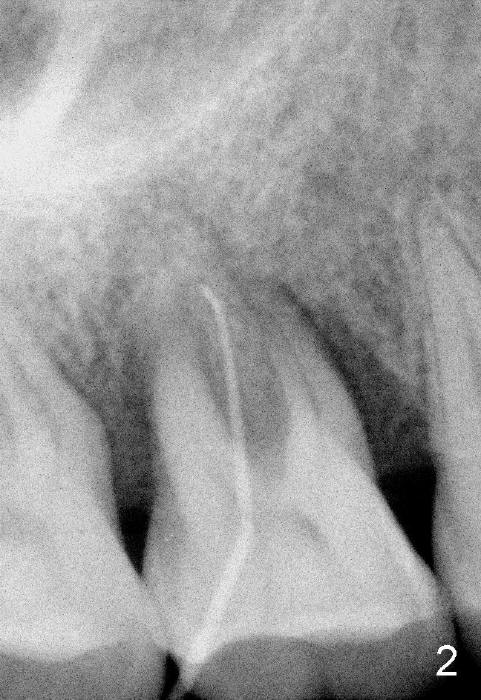

The tooth #3 has severe periodontitis with probably endodontic lesion (Fig.1,2). The patient is a 43-year-old man with apprehension of dentistry. An acute infection causes pain and tooth shift (Fig.4,5). A 7x17 mm immediate implant is planned (Fig.3). The palatal socket is shallow (Fig.6 P), corresponding to severe recessive palatal root (Fig.5 P). The osteotomy is created mainly in the buccal socket (Fig.6 B), exactly in the lingual slope of the septum. Initially osteotomes are used, followed by tap placement (Fig.7 T (4.5x20 mm at the depth of 17 mm). When the implant is placed as planned (Fig.8 I), there is more vertical contact (Fig.8 red line) than that associated with the tap (Fig.7 red line). The corresponding insertion torque is between 50 and 60 Ncm. There is only one small gap buccally, which is filled with bone graft (Fig.9 <). After the insertion of a short abutments with vertical slots (Fig.9,10 A), perio dressing is used to cover the wound. The palatal socket is expected to heal uneventfully (Fig.10 P). In fact, it does in 7 days (Fig.12 P); the bone graft in the mesiobuccal aspect is healing and stabilized (Fig.11 <). By two weeks postop, the mesiobuccal socket has healed (Fig.13 <). With removal of a diseased tooth, our body has amazing power to heal.